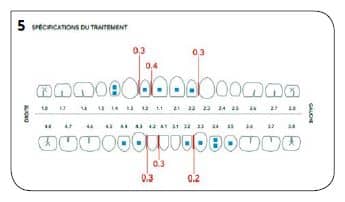

Suites aux examens, nous avons réalisé un premier ClinCheck permettant d’avoir un premier repositionnement (Fig.5). On peut ici constater :

– une série de 17 aligneurs,

– une série de réductions inter-proximales maxillaires (RIP) pour un total de 1,0 mm réparties entre les 15 et 25,

– une série de réductions inter-proximales mandibulaires (RIP) pour un total de 0,8 mm réparties entre les 15 et 25,

–des taquets répartis sur toutes les dents maxillaires pour optimiser les mouvements voulus,

– des taquets sur quelques dents maxillaires.

La durée du traitement est de 34 semaines avec un changement des aligneurs toutes les 2 semaines (Fig.5 à 7).